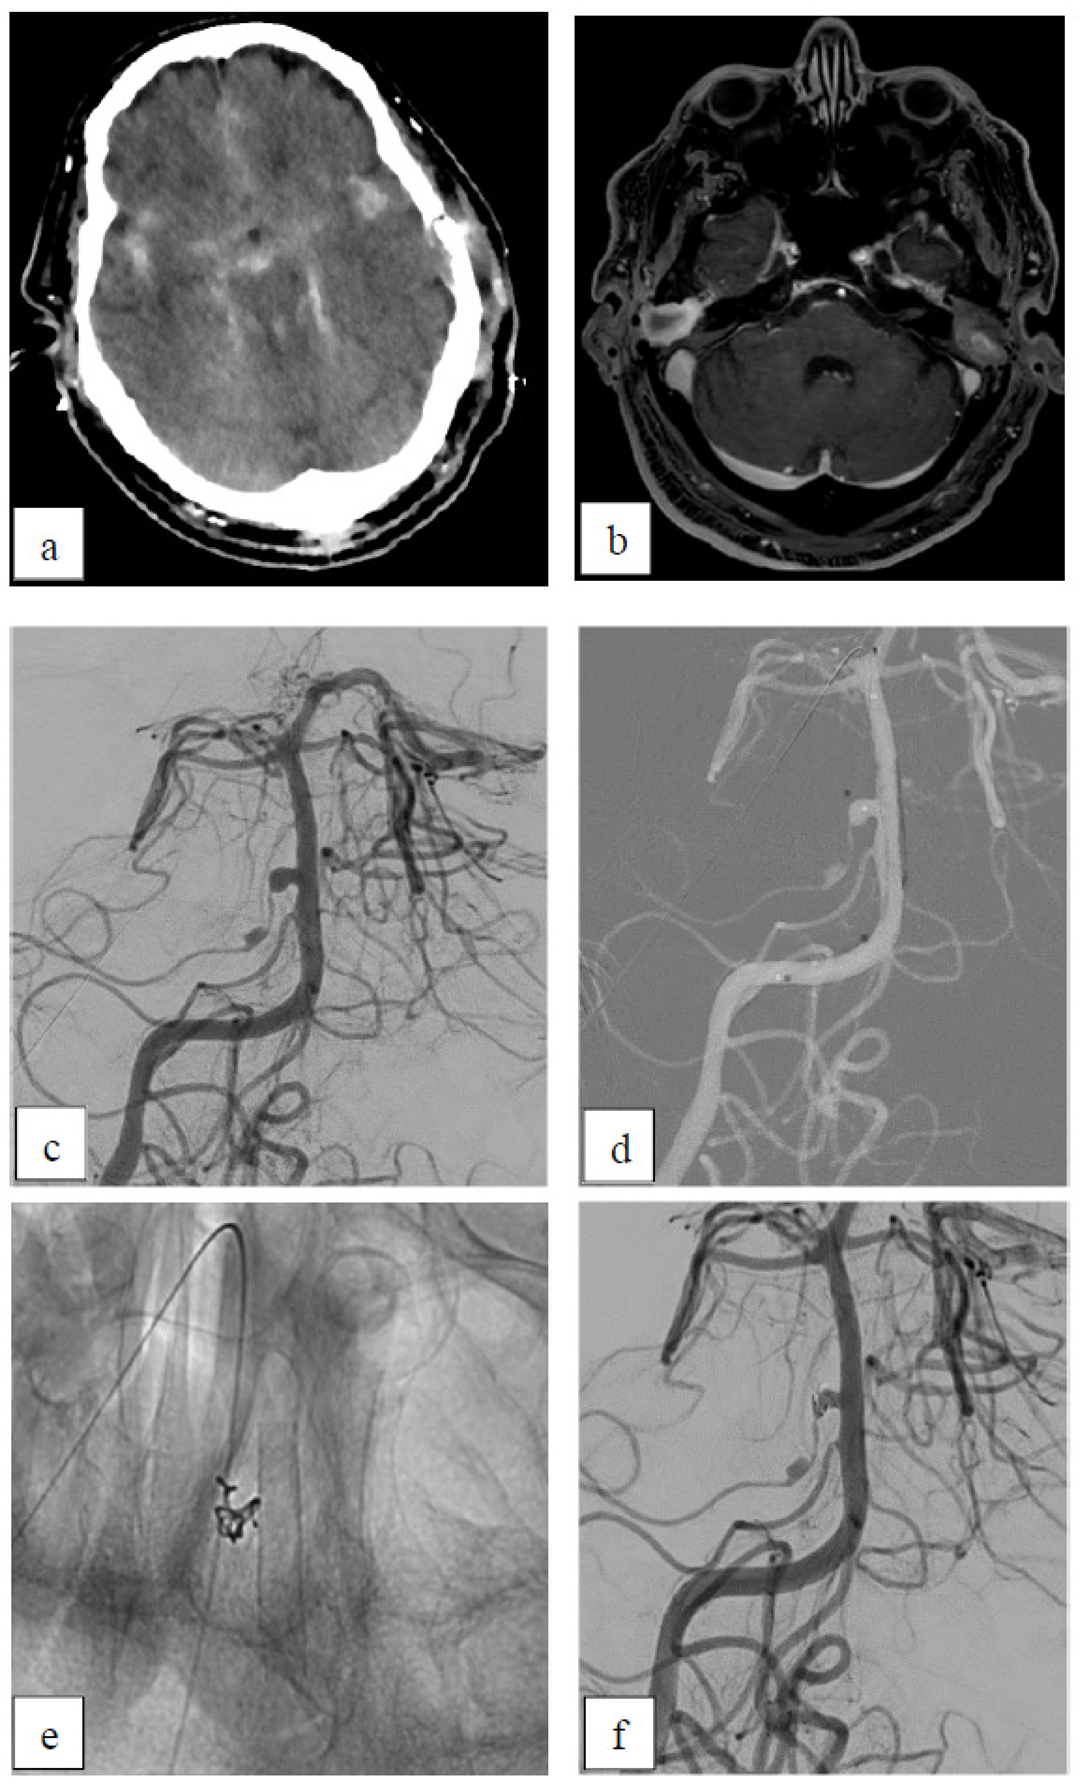

Case 4: Dissecting Aneurysm

Case 5: Inflammatory Aneurysm

| 28 | f | P2/P3 | right | dissecting | yes | no | ASA+ Clopidogrel | A2 | 5 | D1 |

| 48 | m | V4 | left | dissecting | yes | no | ASA+ Clopidogrel | A3 | 6 | D1 |

| 60 | f | V4 | left | dissecting | yes | no | ASA | A3 | - | - |

| 67 | m | AICA (2 aneurysms) | right | inflammatory | yes (SAH) | no | ASA | prox: B3 dist: A3 | - | - |

| 4 | 48 | m | V4 | left | dissecting | yes | no | ASA+ Clopidogrel | A3 | 6 | D1 |

| 5 | 67 | m | AICA (two aneurysms) | right | inflammatory | yes (SAH) | no | ASA | prox:B3 dist: A3 | - | - |